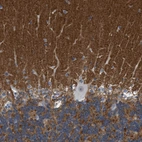

Immunohistochemistry analysis in human cerebral cortex and pancreas tissues using HPA014447 antibody. Corresponding PRRT2 RNA-seq data are presented for the same tissues.